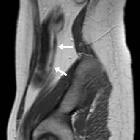

Crohn's disease in the appendix

MRI

MR enterography has become an increasingly important part of the management of patients with Crohn disease. MR enteroclysis may be attempted in select patients.

MR enterography (MRE)

- stricture: focal narrow of the lumen with immediate upstream bowel dilatation >=3 cm. Bear in mind that sometimes the upstream loop is not dilated to size criterion due to decompression by a fistula/penetrating disease or limited bowel content inflow in the setting of two or more consecutive stricture segments

- highly suspected stricture should be reported in persistent focal luminal narrowing across multiple MRI sequences

- although they can be divided as fibrotic or inflamed strictures, the majority will have a component of active inflammation

- location and length of the stricture should be reported

- strong association of strictures and penetrating disease, so one should prompt the evaluation for the other

- stricture vs obstruction: upstream dilatation over 4 cm is advised to be reported as small bowel obstruction

- ulcerations: focal defect at the intraluminal aspect of the small bowel wall, confined within the serosa (cf. sinus tract)

Features of penetrating disease include:

- sinus tract: blind-ended tract extending beyond the bowel serosa

- fistula tract: tract that communicates the bowel lumen to another epithelialize surface

- usually seen proximal to a small bowel stricture

- active inflammation is almost always present

- complex fistula: more than one tract associated with angulation or tethering of affected loops

- inflammatory mass: mesenteric stranding (on CT) or increased T2 signal denoting inflammation but without fluid collections

- abscess: a fluid collection with rim-enhancement